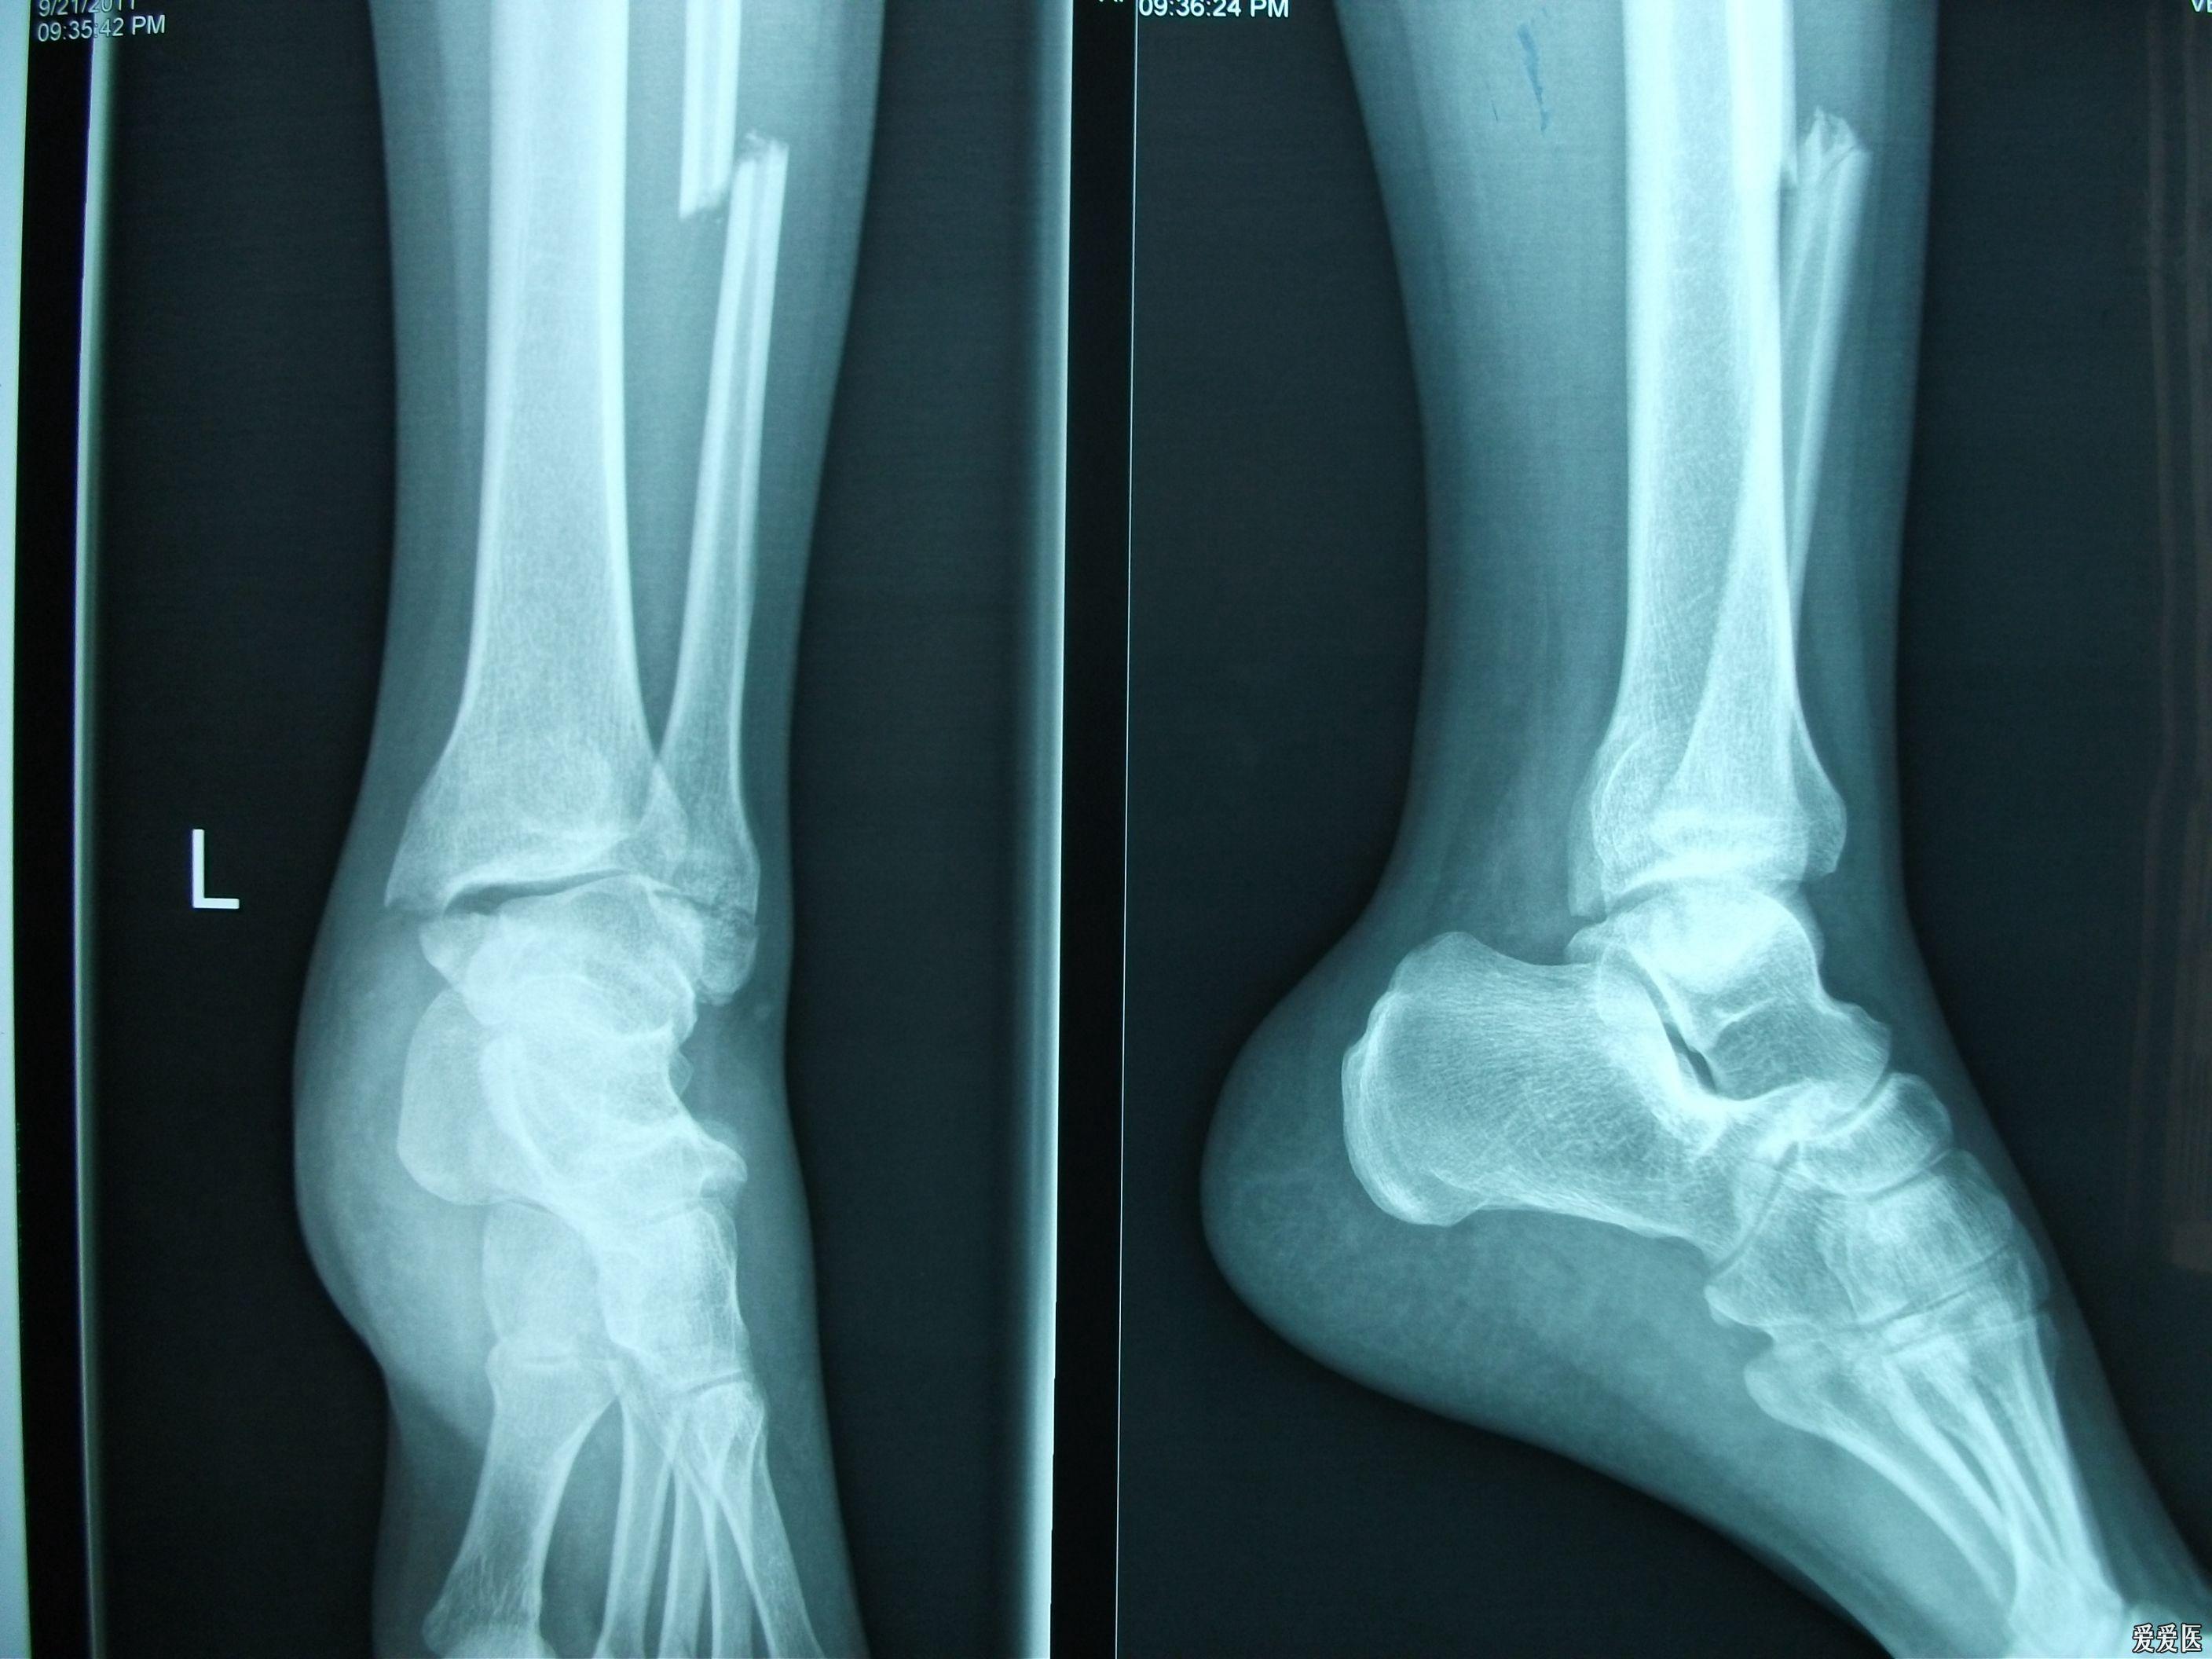

右脚踝扭伤,腓骨骨折,关节移位.请看x光片,谢谢.

左踝关节肿胀 辅助检查:x线片提示:左踝关节骨折,左侧腓骨骨折 临床

踝关节骨折一例